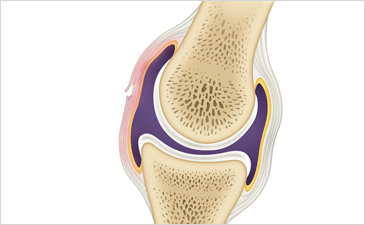

슬개골인대손상이란?

슬개골인대손상은 무릎 주위 인대가 강한 외부의 충격이나 무리한 사용으로 찢어지거나 파열되어 일상생활에 불편을 주는 질환입니다. 무릎 인대는 많이 사용하면 할수록 약해져 부분적으로 손상을 일으키기 쉬우며 슬개골인대손상은 무릎 옆쪽인대 손상, 전방 십자인대 손상, 후방 십자인대 손상으로 나누어집니다.

슬개골인대손상 증상

- 무릎에서 퍽 하며 찢어지는 느낌이 든다.

- 무릎이 아프고 붓는 관절 부종이 나타난다.

- 손상된 부위에 압통이 나타난다.

- 일상적 보행이나 스포츠 활동 중에 무릎의 무력감이 느껴진다.

- 심한 경우 관절강내 출혈이 나타날 수 있다.